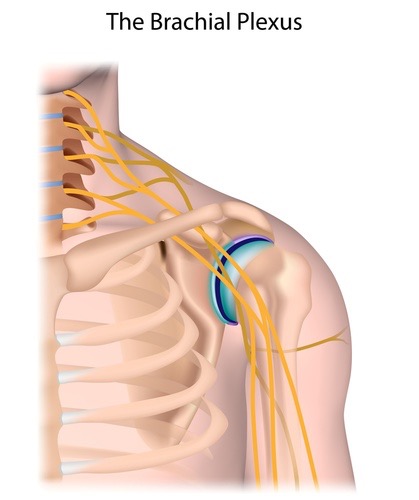

このセッションでは、血管・靭帯・神経をあなたの臨床に取り入れやすくするために筋膜との関係性を明らかにします。例えば腕神経叢は斜角筋と繋がりがありますし、坐骨神経は梨状筋との繋がりがあります。この知識さえあれば、どのタイミングで血管や神経を見ればいいのかがわかり。明日からの臨床ですぐに結果を出すことができるでしょう。

あなたは腕神経叢の解剖を詳しく知っていますか?どの位置にあって、どの深さにあって、どんな走行で、どの組織の間を通るか、などすぐに答えることができますか?腕神経叢もエコー解剖で丸裸にしたからこそ可能となったリリーステクニックです。他のどのセミナーであっても学ぶことはできません。このテクニックを学ぶことであなたは、、、